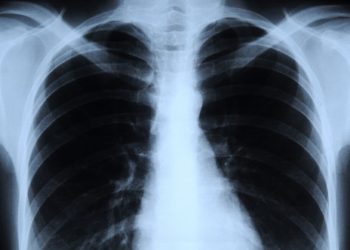

ما هي الأشعة السينية؟ كيف نستخدمها؟؟ وما هي المخاطر الناجمة عن استعمالها ؟؟ ما هي الأشعة السينية؟ الأشعة السينية هي...